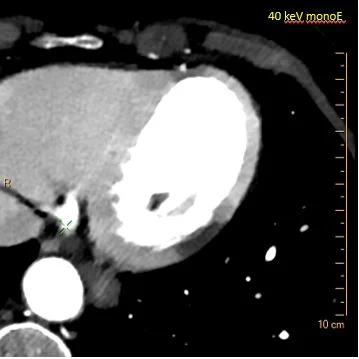

40 keV image: How can anyone miss the MI?